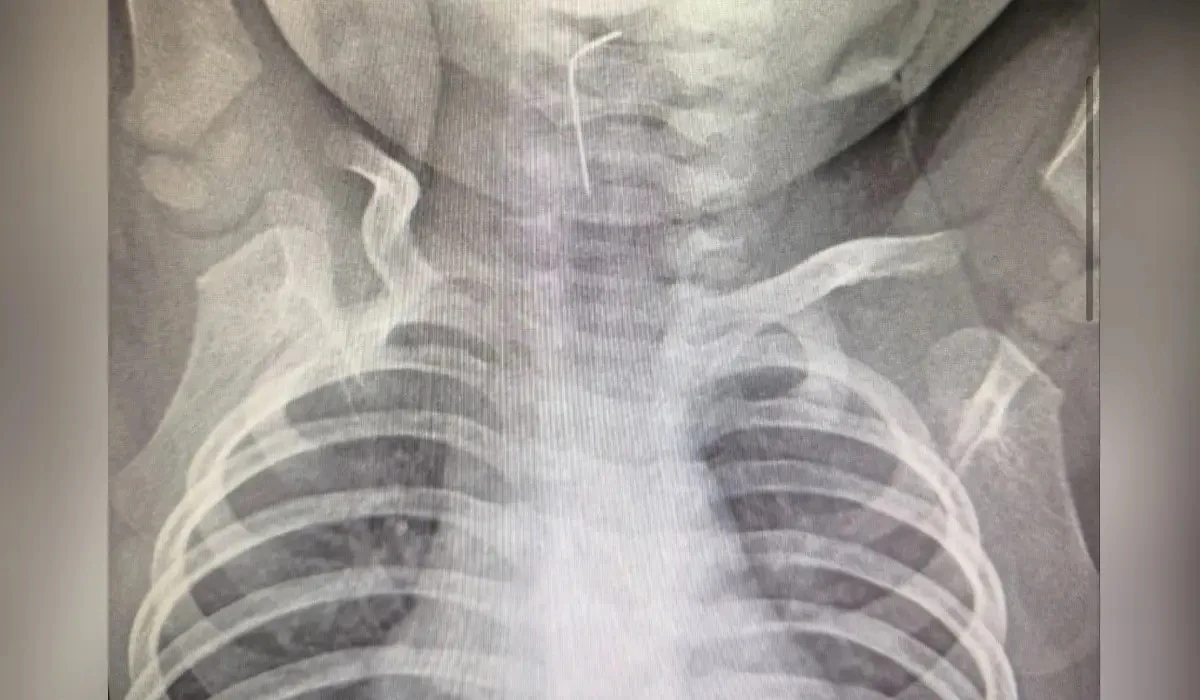

Дәрігерлер рентгенологиялық тексеру жүргізіп, эндоскопиялық әдіс қолданды. Мамандар бөгде заттың нақты орналасқан жерін анықтап, өңешке қадалған инені сәтті алып шықты.